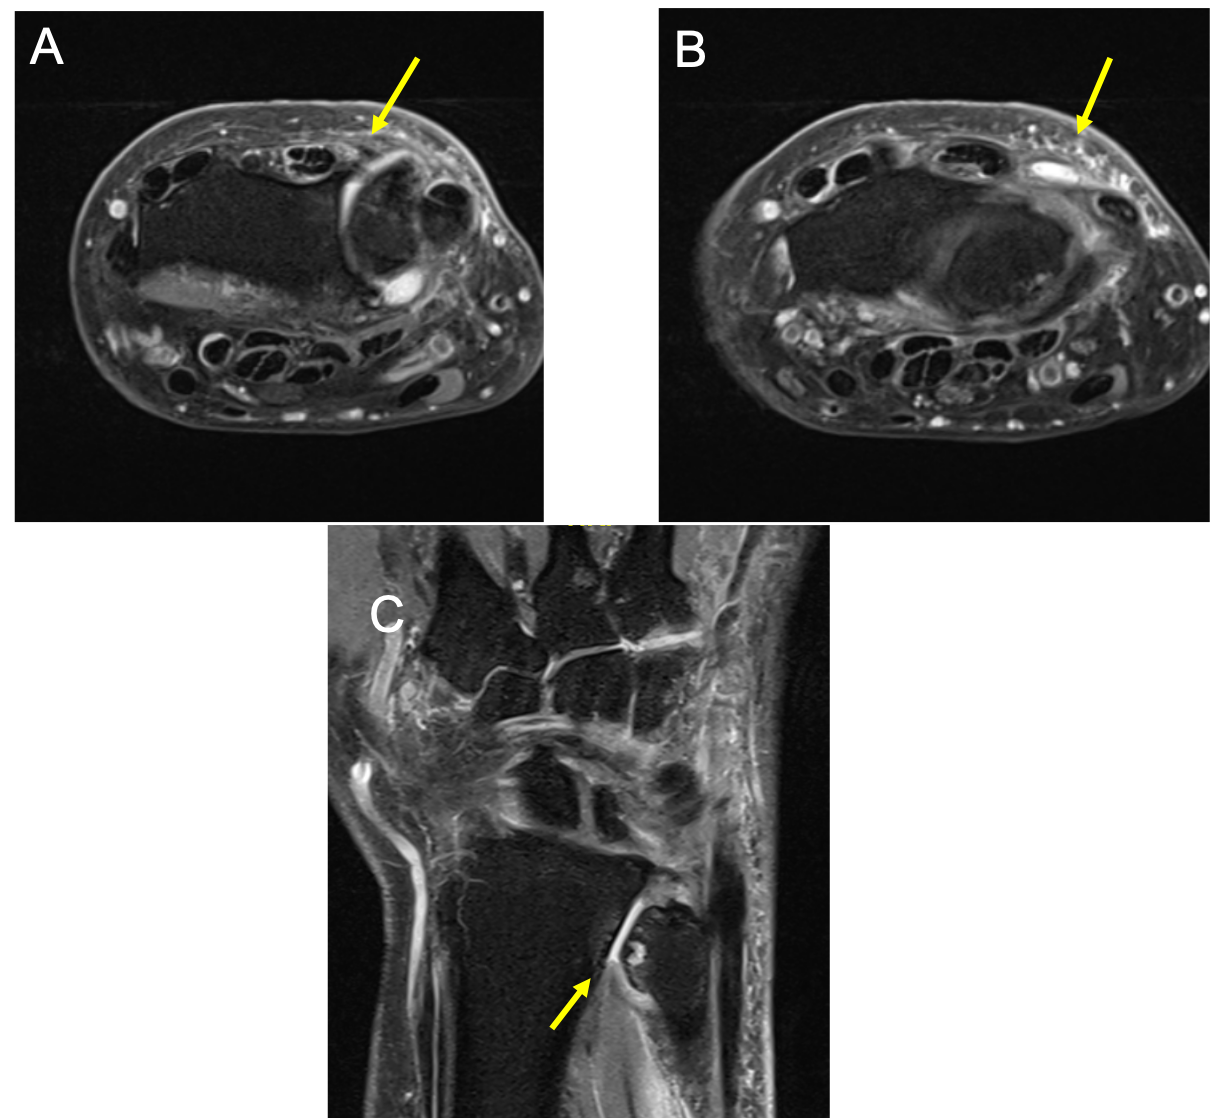

Magnetic resonance imaging (MRI) study of the right wrist and hand revealed osteoarthritis of the DRUJ with a prominent osteophyte projecting dorsally and causing impingement of the EDM tendon at the level of the DRUJ, which is attenuated. These findings were consistent with ulnar impingement syndrome. Complete rupture of the EDM tendon with tenosynovitis was noted distal to the DRUJ to the level of the first row of carpal bones (Figure 3). Distally, the tendon was noted to be intact. The EDC tendon to the little finger was not visualized and presumed to be torn. The EDC tendons to the rest of the fingers were observed to be intact.

Figure 3. (A) Axial PD fat-saturated MRI sequence at the level of the DRUJ demonstrates prominent dorsal osteophyte causing impingement of the EDM tendon, which is attenuated. (B) More distally, there is complete rupture of the EDM tendon at the level of the proximal carpal row. (C) Coronal PD fat-saturated image demonstrates negative ulnar variance with osteoarthritic changes at the DRUJ, with subchondral cysts and oedema, and small joint effusion.